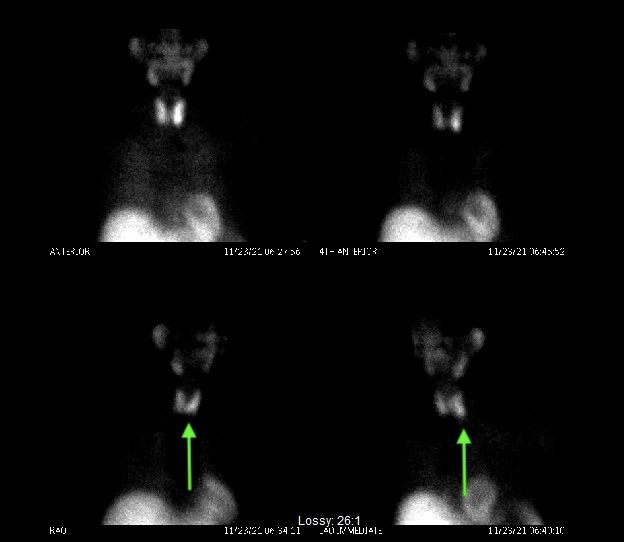

On the day of surgery, his scan suggested two separate tumors, both on the right side. These scans usually show only one or no tumors. On the lower right image, you can see both the dark spot of the right lower tumor as well as the space between the two thyroid lobes being grayed out. This is usually seen with an upper gland tumor.

Both glands were over-functioning at close to the same level, although the upper gland is about half the size of the lower gland. This is why you want your surgeon to look at all four glands. Had we stopped after taking out the biggest signal, we would have only cured half of his disease. His post-operative parathyroid hormone decreased as expected, consistent with cure. He recovered well and had essentially no pain the night of surgery.